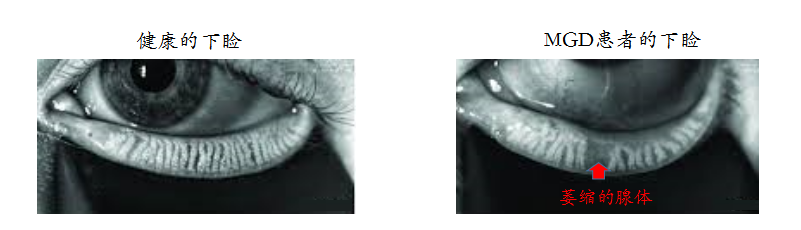

睑闆腺功能障礙(meibomain gland dysfunction,MGD)在油性皮膚及年老者中十分常見(jiàn),是(shì)蒸發過強型幹眼症的主要原因。指睑闆腺終末分泌導管開口堵塞,伴有脂質分泌量異常和/或成分改變;伴慢(màn)性、彌漫性的睑闆腺功能異常;MGD可導緻淚膜異常,出現(xiàn)眼部刺激症狀及眼表炎症反應。

研究表明,炎症介質可改變睑闆腺分泌物睑酯的成份,使蠟酯下降,膽固醇酯升高,增加黏度阻塞導管;睑酯黏度增加爲細菌生長提供載體,細菌大量繁殖,産生毒性介質,使腺泡萎縮,睑酯分泌減少。